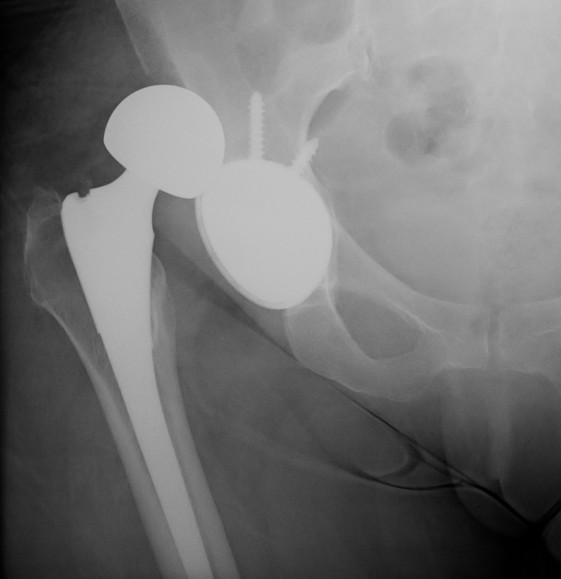

3. Component position

Acetabular safe zones

- inclination 40 +/- 10o

- anteversion 15 - 30o

- 9800 hips

- evaluated Lewinnek safe zone

- cup inclination 40+/-10

- cup anteversion 15+/-10

- 58% of dislocations had cup position within safe zone

4. Component design